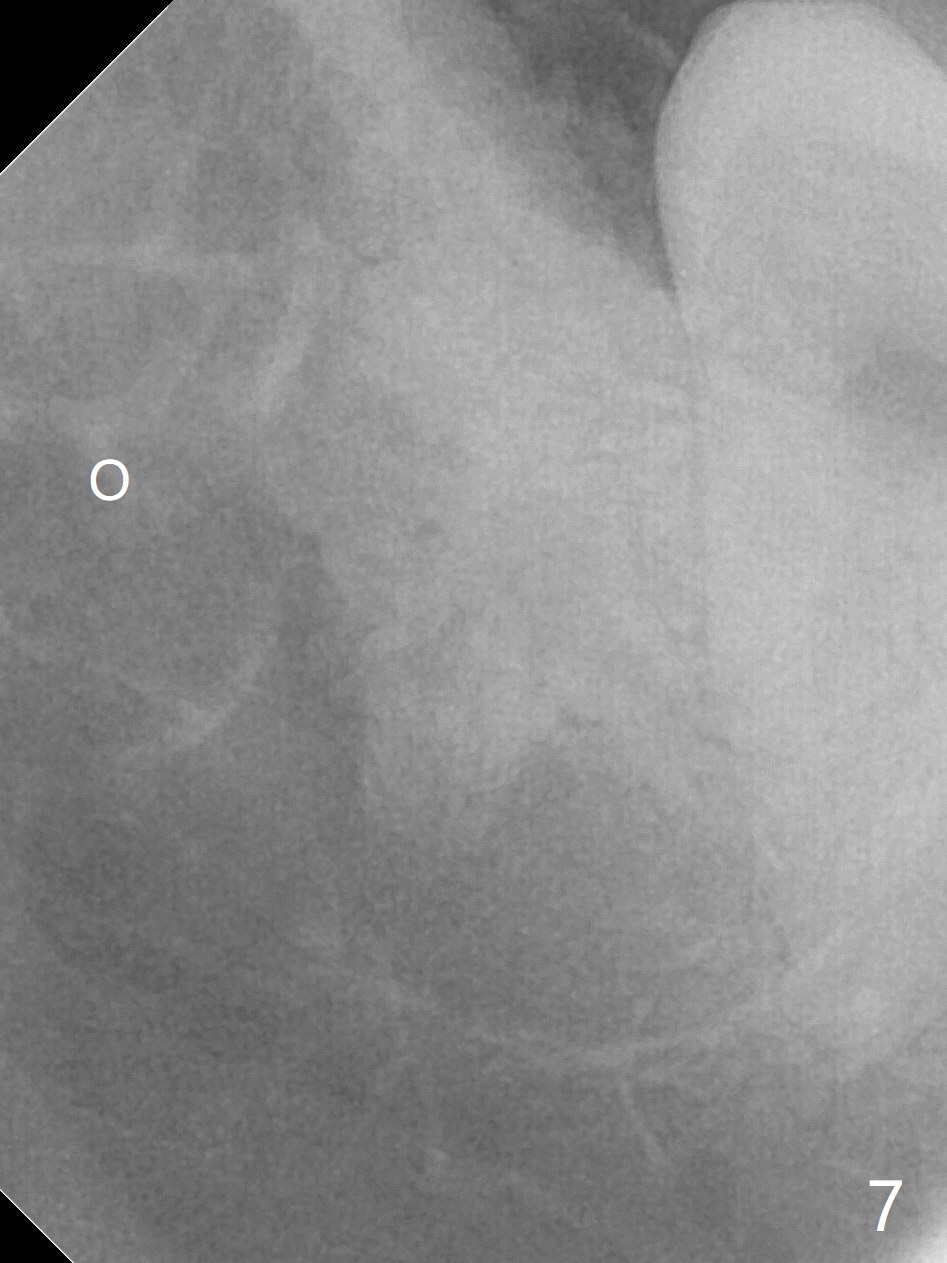

A 17-year-old man will return for extraction of 4 of the 3rd molars (Fig.1). Since the distobuccal surface of the tooth #31 may lack the bone (Fig.2 *), half of Augma will be placed in the distal portion of the sockets of #17 and 32, while allograft in the mesial one. Take PAs immediately post extraction to determine bony defects of the lower 3rd molars. Insert a piece of 2x2 gauze into the socket immediately post extraction. If hemorrhage is severe because of closeness between the mesial roots of the lower 3rd molars and the Inferior Alveolar Canal (Fig.2,3 red dashed line) after removal of the gauze, insert a half piece of Collagen Plug or more into the socket. If the latter is effective in hemostasis, Augma will be not applied, but allograft will be used, followed by Collagen Plug on the top of the allograft and sutures. Prepare both 4-0 and 5-0 ones. In fact the patient chooses to have 2 of the 3rd molars to be extracted. The extraction at #32 turns out to be extremely difficult with numerous sectioning because the crown of #32 is embedded into the distolingual surface of the fused conical roots of #31 (Fig.4,5). After insertion of a whole piece of Osteogen plug (Fig.7 O) into the root portion of the socket, Bond Apatite (1 cc) is pressed into the coronal portion of the socket (Fig.6 A). Due to oozing, the cement does not seem to be set completely. One third piece of Collagen plug is placed on the top of the cement before 4-0 Chromic gut suturing tightly. CBCT will be taken for better treatment approach prior to #17 extraction. Return to Plug Augma Xin Wei, DDS, PhD, MS 1st edition 10/06/2019, last revision 12/28/2019